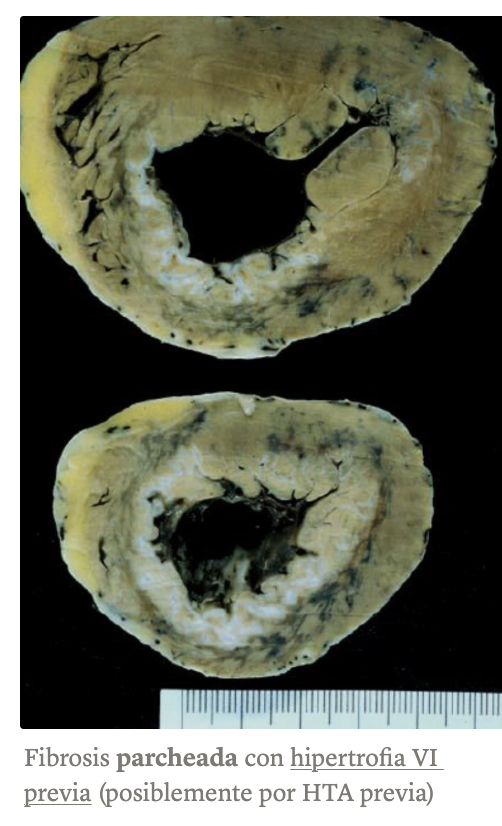

Cardiopatía isquémica crónica